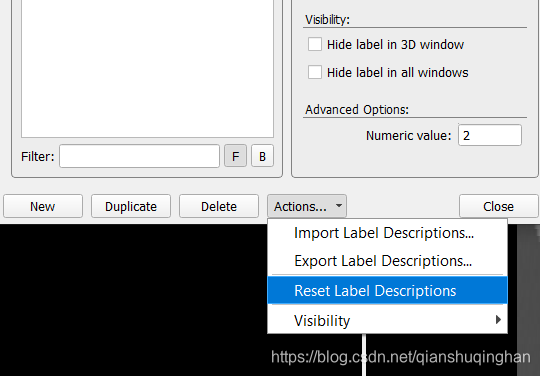

设置和导入导出标签

从菜单栏Segmentation->Label Editor进入如下界面,可手动修改label命名、从而更直观。

通过Actions,可以保存和导入自定义的label模板